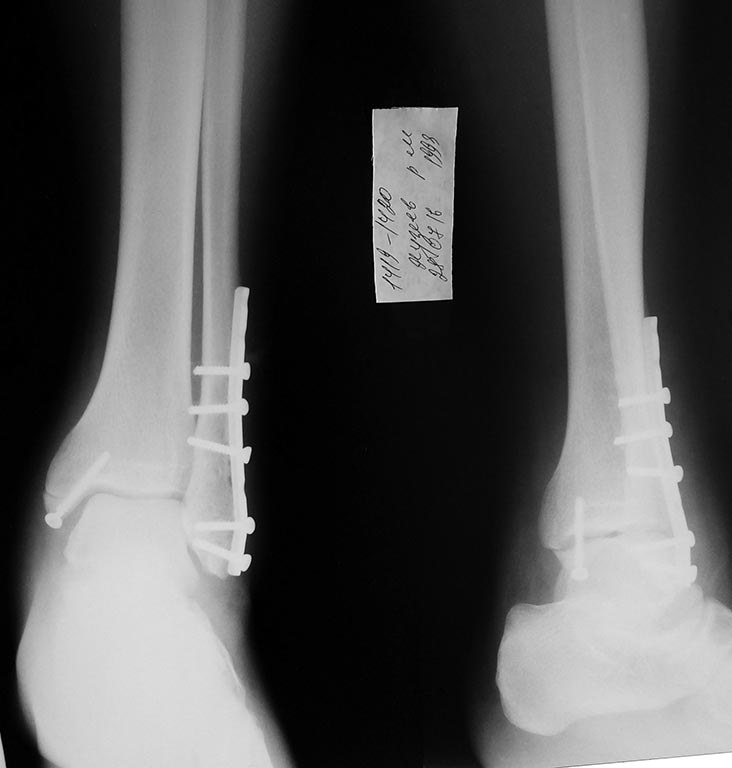

Отправитель: Бек 24 Июль 2016, 10:43

Не смог поставить позиционного винта

Так как отверсти пластины не совпадал перпендикулярно к ББК

Re: Разрыв межберцового синдесмоза

ТРАВМА 15.07

Так то банальный перелом в этот раз не получилось стандартную операцию выполнять

Смотрел на Первый снимок

Наверно здесь синдесмоз не разорван

Решил откусить винтика

Поэтому на снимке, после остеосинтеза лодыжек, я не хочу видеть подвывих. Тем более явный.

NB: Чем выше произошел перелом наружной лодыжки, тем вероятнее и грубее разрыв межберцового синдесмоза!!! Это потребует операции, даже при идеальной репозиции отломков и красивом снимке в гипсе. Даже если нет подвывиха тарана на первичном снимке.

В случае автора темы, перелом наружной лодыжки на уровне синдесмоза ( я называю это "чрезсиндесмозный" перелом лодыжки), и есть разрыв передней (по личному опыту) порции синдесмоза. Синдесмоз нестабилен, будет подвывих тарана. Это требует фиксации синдесмоза винтом. Винт проводится через малоберцовую кость в большеберцовую под углом 25-30* сзади наперед в фронтальной плоскости. Винт проводится горизонтально линии голеностопного сустава (я ее маркирую на коже). Обычно это делается через одно из отверстий пластины (бывает, что его приходится рассверлить до диаметра резьбы винта перед или в момент операции сверлом по металлу). Можно поставить винт вне пластины, используя шайбу или обрезок пластины с 1 отверстием (не выкидываю обрезки). Винт нужно стремиться расположить как можно ниже к суставу, но не ближе 1 см. Т.е. на уровне физиологичного синдесмоза.